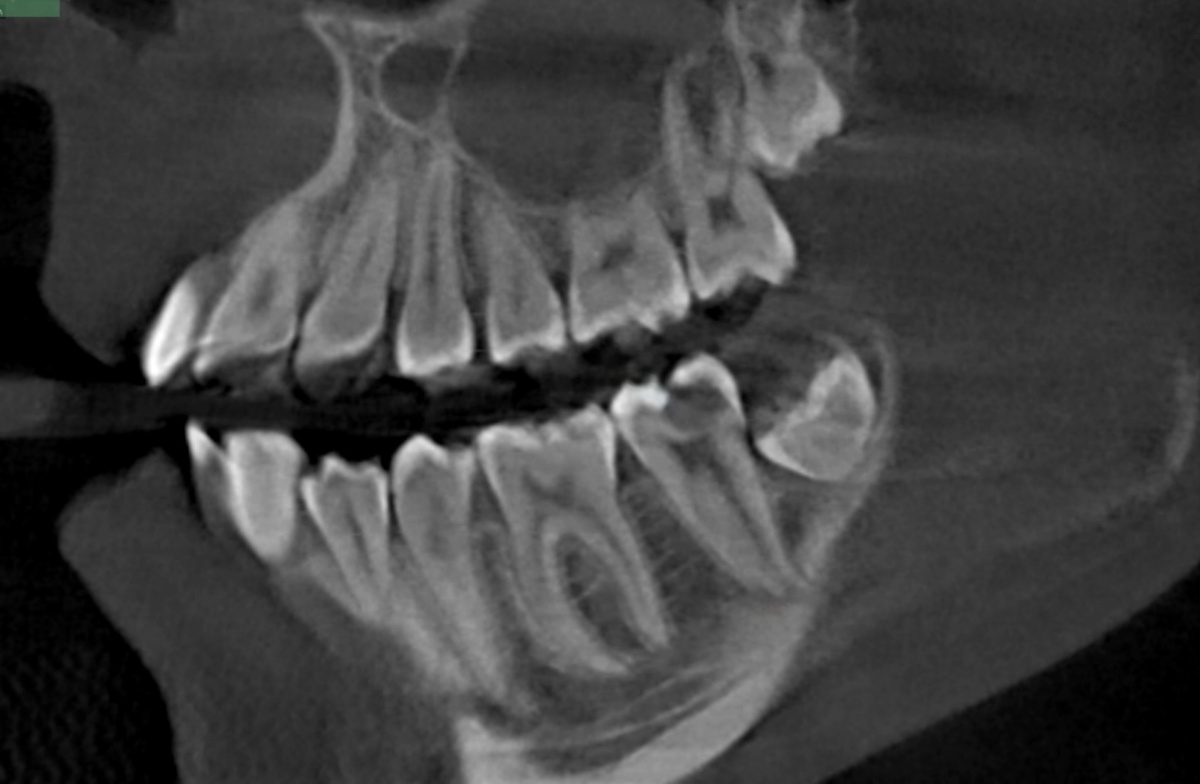

Сделали КТ. Картина оказалась неожиданной и пугающей - три больших кариеса. Сразу три больших кариозных поражения у человека, которому нет и двадцати и которому на каждом приёме говорили, что всё нормально.

Самым срочным оказался 3.7 зуб - нижняя семёрка слева. На него и обратили внимание в первую очередь:

На момент консультации зуб выглядел почти целым. Никаких жалоб - ни боли, ни реакции на горячее, ни ночных приступов. Единственное, что заметила сама пациентка к моменту лечения - небольшой скол стенки. Вот и всё.

Но снимок говорил другое - кариес был огромным.